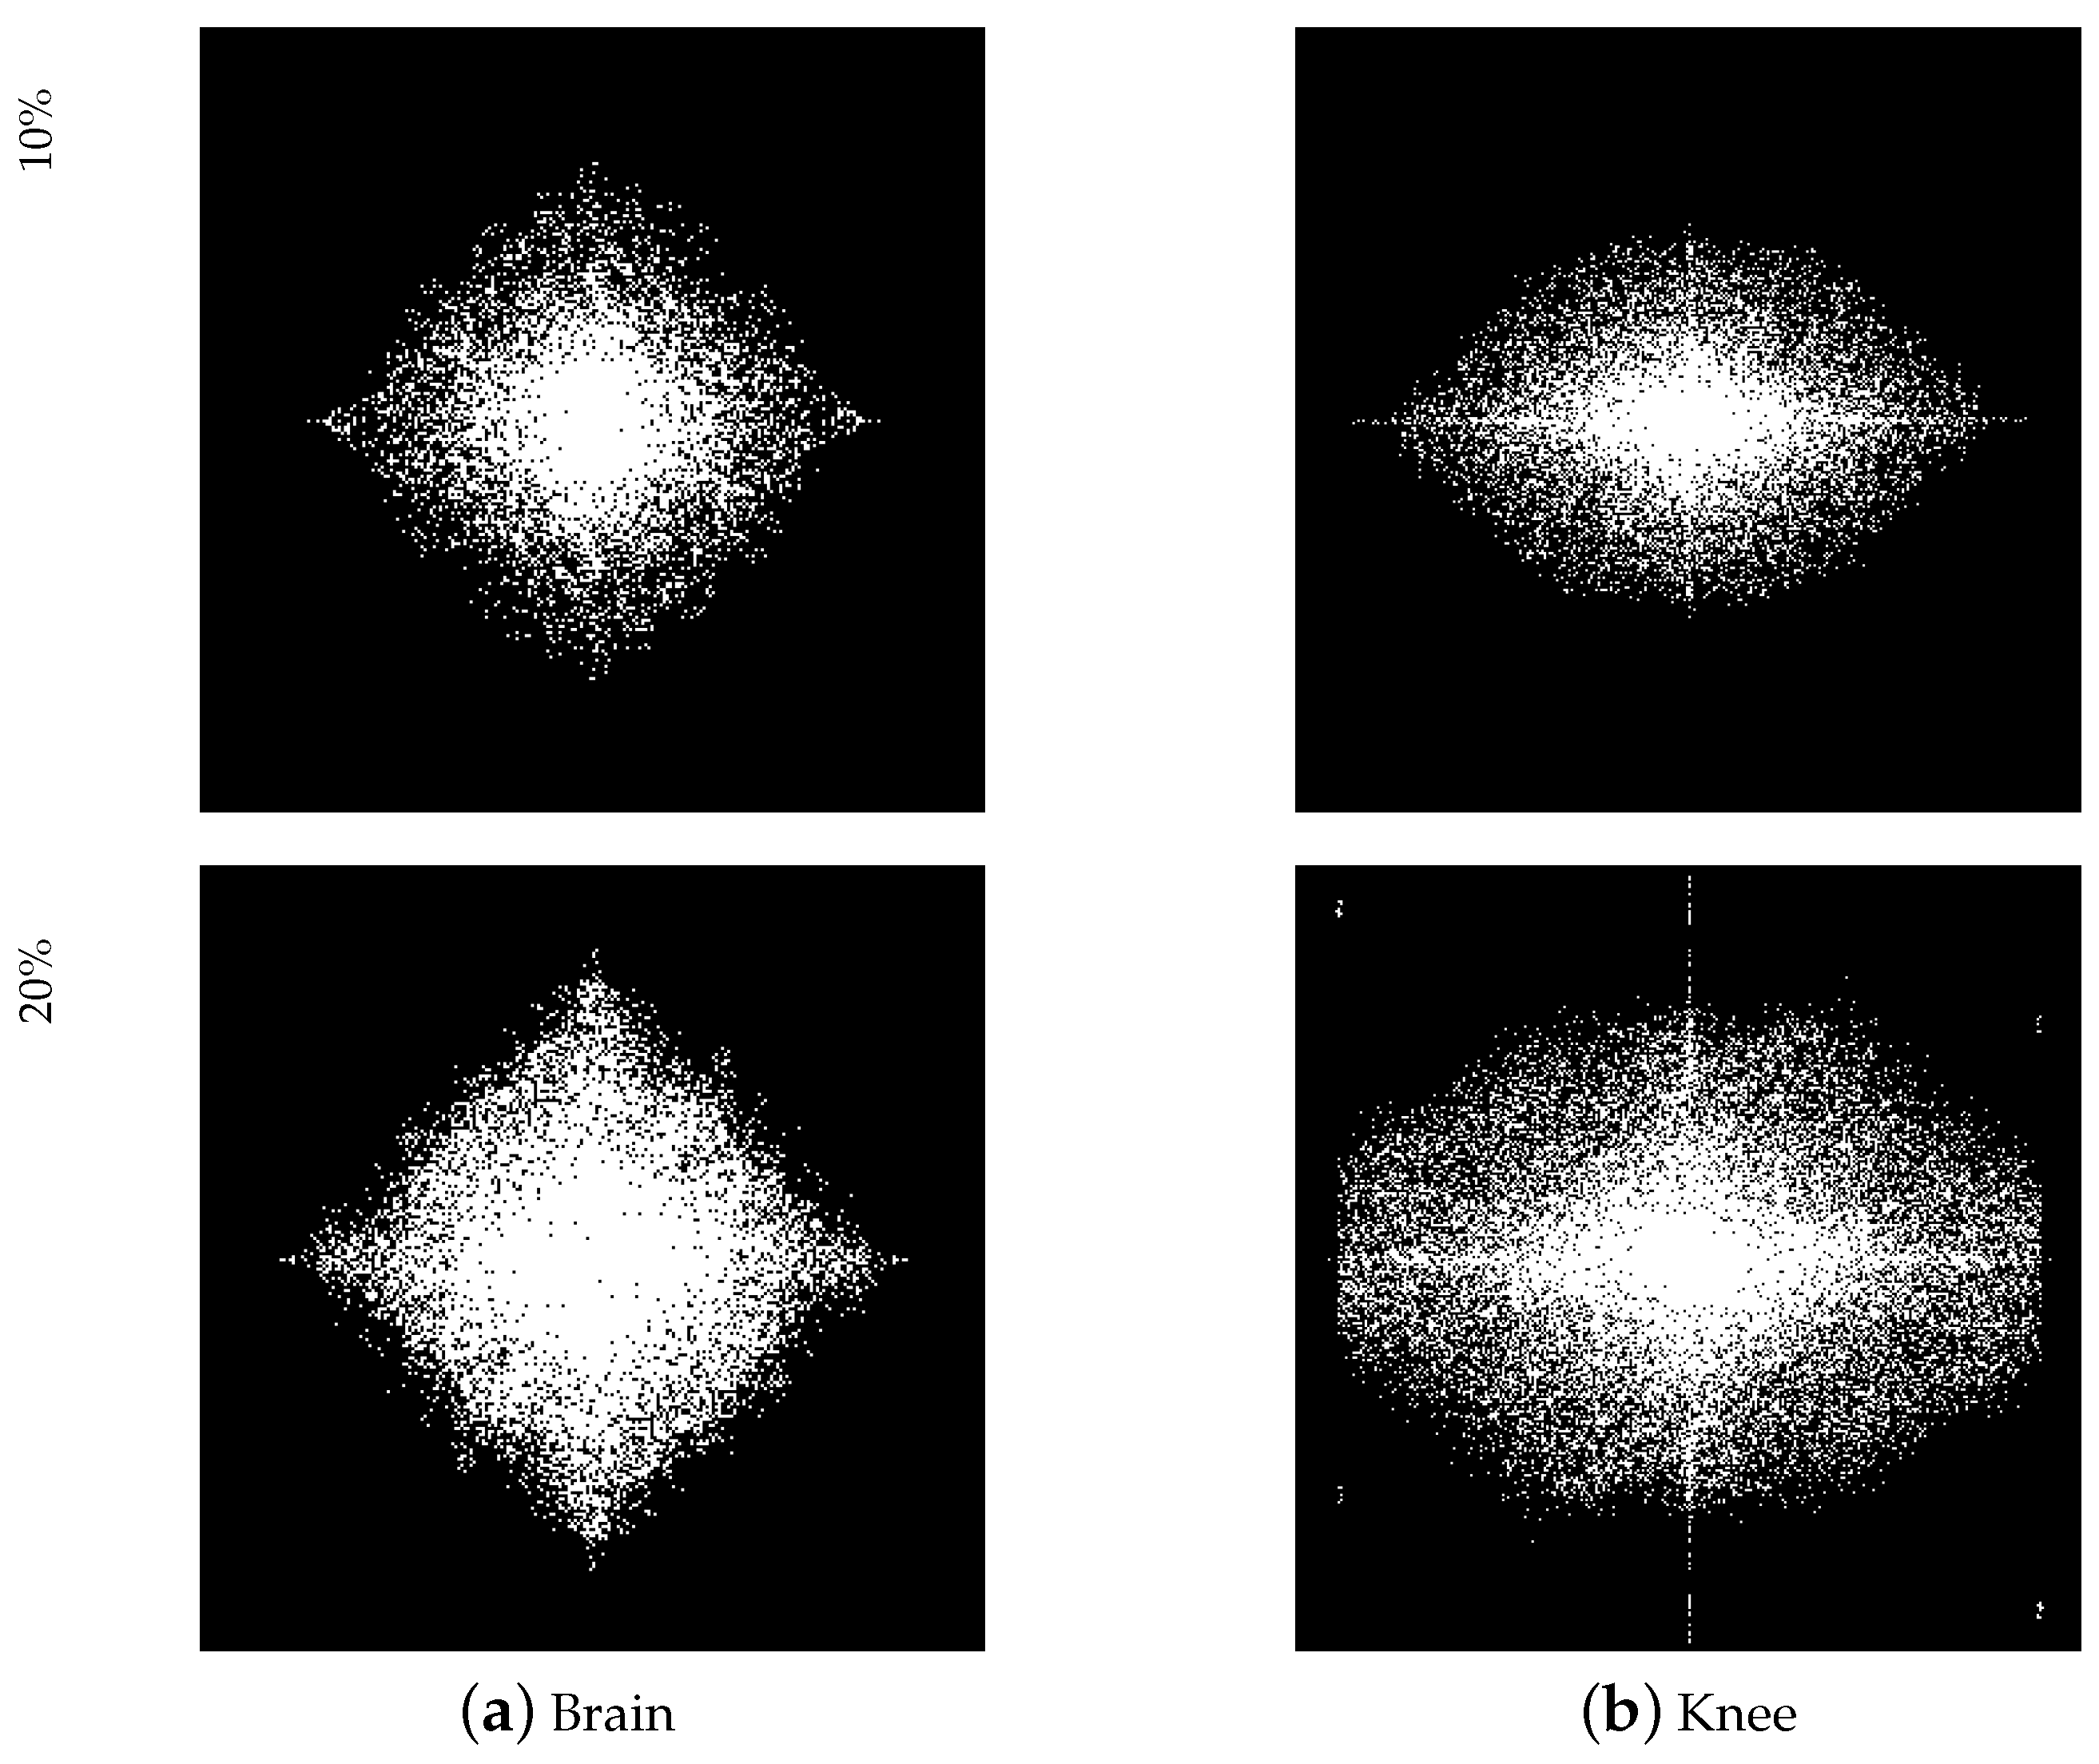

Figure 4 shows a visual comparison between the classical mask and our trained optimized sub-sampling ratio for | | S | | 0 = 10 % and | | S | | 0 = 20 % . It can be seen that the learned 2 D mask exhibits a strong preference for lower frequencies and a denser sampling pattern closer to the origin of K-space, which is also in line with prior knowledge, i.e., the lower frequency part has greater energy.

In addition, Figure 6 compares the differences in the anatomical optimization of the knee and brain joints of our model. We observed that for MR images of the knee, due to the unique asymmetrical features of knee anatomy, give more importance to the lateral frequency direction, with obvious tissue contrasts. Conversely, the masks learned on the Brain dataset appear to be more balanced in all frequency directions. Such data comparison results show the importance of learnable masks, and it is necessary to customize sampling masks of different structures for data with different structures. It is worth noting that the masks learned on the Brain and Knee datasets at 10 % show high intermediate density and low peripheral density. At 20 % , the Knee mask maintains this feature, but the Brain mask has a high density within its data structure, which may indicate that the sampling ratio of 20 % is good enough to restore good results for the Brain dataset but not for the Knee dataset. The experimental results given in Table 2 also illustrate this.

Figure 6. Visual comparison of learned masks on Brain and Knee datasets with CS ratios of 10% and 20%. The masks learned on the Knee dataset appear to give more importance to the lateral frequency direction, with obvious tissue contrasts, while the masks learned on the Brain dataset appear to be more balanced in all frequency directions.